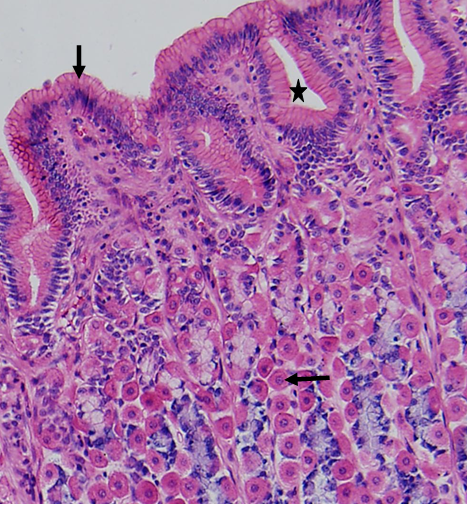

图3. 胃黏膜光镜像(HE染色)

可见胃黏膜上皮为单层柱状上皮,除少量内分泌细胞外主要由表面黏膜细胞组成。该细胞柱状,细胞核位于基底部,顶部胞质充满黏原颗粒,染色淡。表面黏液细胞分泌含高浓度HCO3-的不溶性黏液,构成黏液-碳酸氢盐保护屏障,该屏障的破坏,可形成胃溃疡。固有层的胃底腺中可见嗜酸性胞质染成红色的壁细胞,壁细胞除了产生盐酸外,还分泌内因子,内因子可防止维生素B12的分解和并促进其吸收。内因子的缺乏(萎缩性胃炎,胃大部切除等情况),维生素B12缺乏,可致恶性贫血。